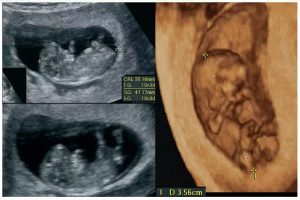

Diplomados en Ultrasonografía